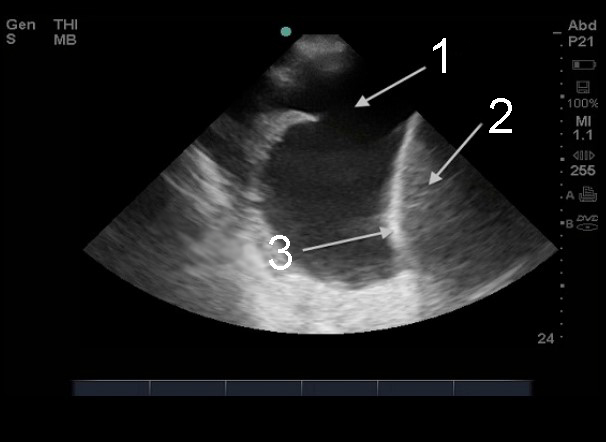

胸腔穿刺、胸水右上四半部(RUQ)1の画像

液体

肝臓

横隔膜